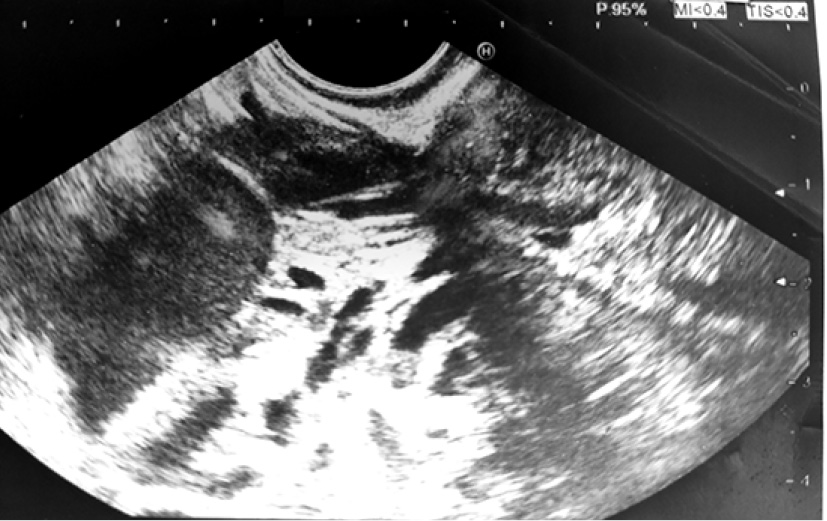

- МРТ с контрастированием от 11.06.2019 г. Заключение: Объёмное образование брюшной полости слева, кистозно-солидной структуры со сдавлением желудка (tumor). Множественные кисты обеих долей печени. Конкремент желчного пузыря. Увеличенные забрюшинные лимфатические узлы (рис. 1–4).

Рис. 1. Увеличенные забрюшинные лимфатические узлы

Рис. 2. Увеличенные забрюшинные лимфатические узлы

Рис. 3. Увеличенные забрюшинные лимфатические узлы

Рис. 4. Увеличенные забрюшинные лимфатические узлы